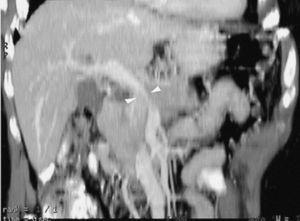

La TC helicoidal permitió, además, llevar a cabo un estudio detallado de los pequeños vasos arteriales y venosos peripancreáticos24-26 (fig. 2), mostrando mejores resultados que la angiografía por sustracción digital en el diagnóstico de la invasión vascular por cáncer de páncreas27. La valoración de estas pequeñas estructuras vasculares mejora el rendimiento de la TC en la estadificación tumoral28,29. La posibilidad de reconstruir en diferentes planos del espacio las imágenes axiales obtenidas ha sido evaluada por algunos autores30,31, obteniendo un mayor rendimiento de la TC para determinar la invasión vascular, fundamentalmente venosa, cuando las secciones transversas se interpretan en combinación con las reconstrucciones multiplanares que cuando se interpretan únicamente las secciones transversas (92-96% frente a 69-70%) (fig. 3).

Fig. 2.--Estudio de tomografía computarizada con contraste endovenoso en fase pancreatográfica en un paciente con neoplasia del cuerpo pancreático. Múltiples vasos mesentéricos dilatados secundarios a la infiltración venosa portomesentérica tumoral (flechas).